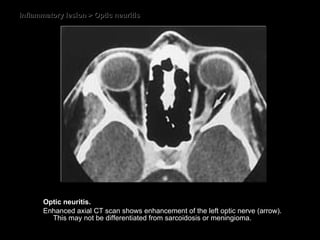

Inflammatory lesion > Optic neuritis Optic neuritis.  Enhanced axial CT scan shows enhancement of the left optic nerve (arrow). This may not be differentiated from sarcoidosis or meningioma.